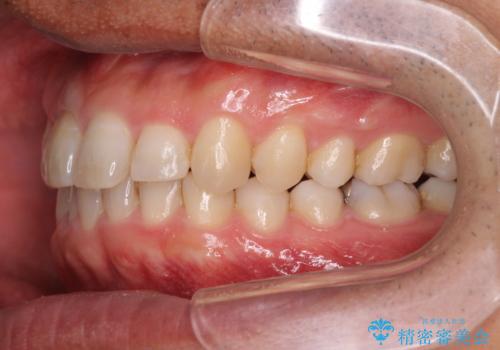

2級ディープバイト 遠心移動を伴うマウスピース矯正

・深い噛み合わせ(ディープバイト) ・2級性の咬合関係(上顎前突)・前歯のがたつき

深い噛み合わせと上顎前突の状態を治すのに時間がかかりましたが、治療後は理想的で安定した咬合関係となりました。